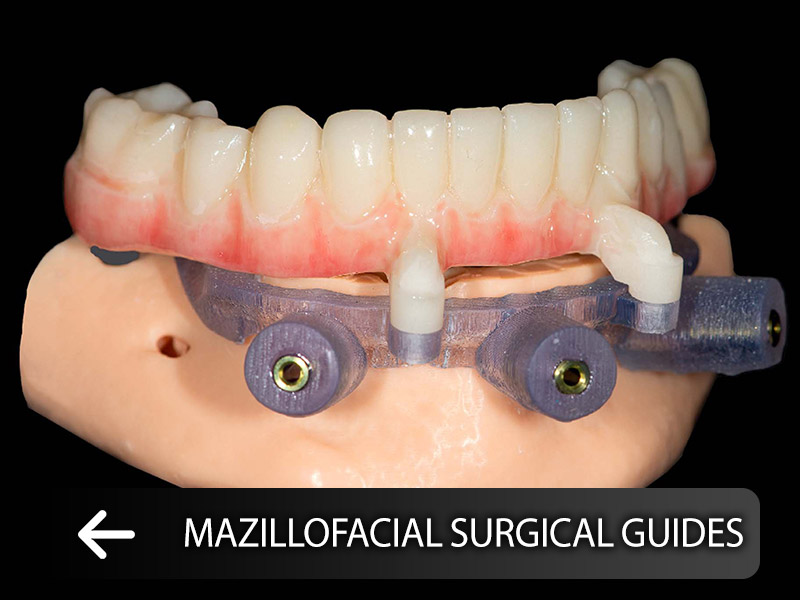

services

The set of digital laboratories of Ganjineh Teb Arman Company provides a complete set of stages from the treatment plan to the manufacture of therapeutic aids and prosthetics by using the skills of experienced technicians and expert dentists..Login and register in the system